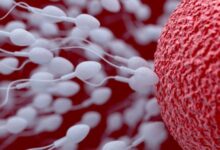

إنّ عدم ثبات الحمل هو عدم استقرار الحمل، أو ضعف الحمل، مما يُعيق استمراره، ونجاحه حتى الوصول إلى مرحلة الولادة، أي بلوغ الشهر التاسع، وهذا ما يؤدي في المُحصلة إلى حدوث الإجهاض، وخسارة الجنين، وهناك العديد من الأسباب التي تقف وراء عدم ثبات الحمل، لا سيما خلال الشهر الأول، وسنتعرف على تلك الأسباب في هذا المقال.